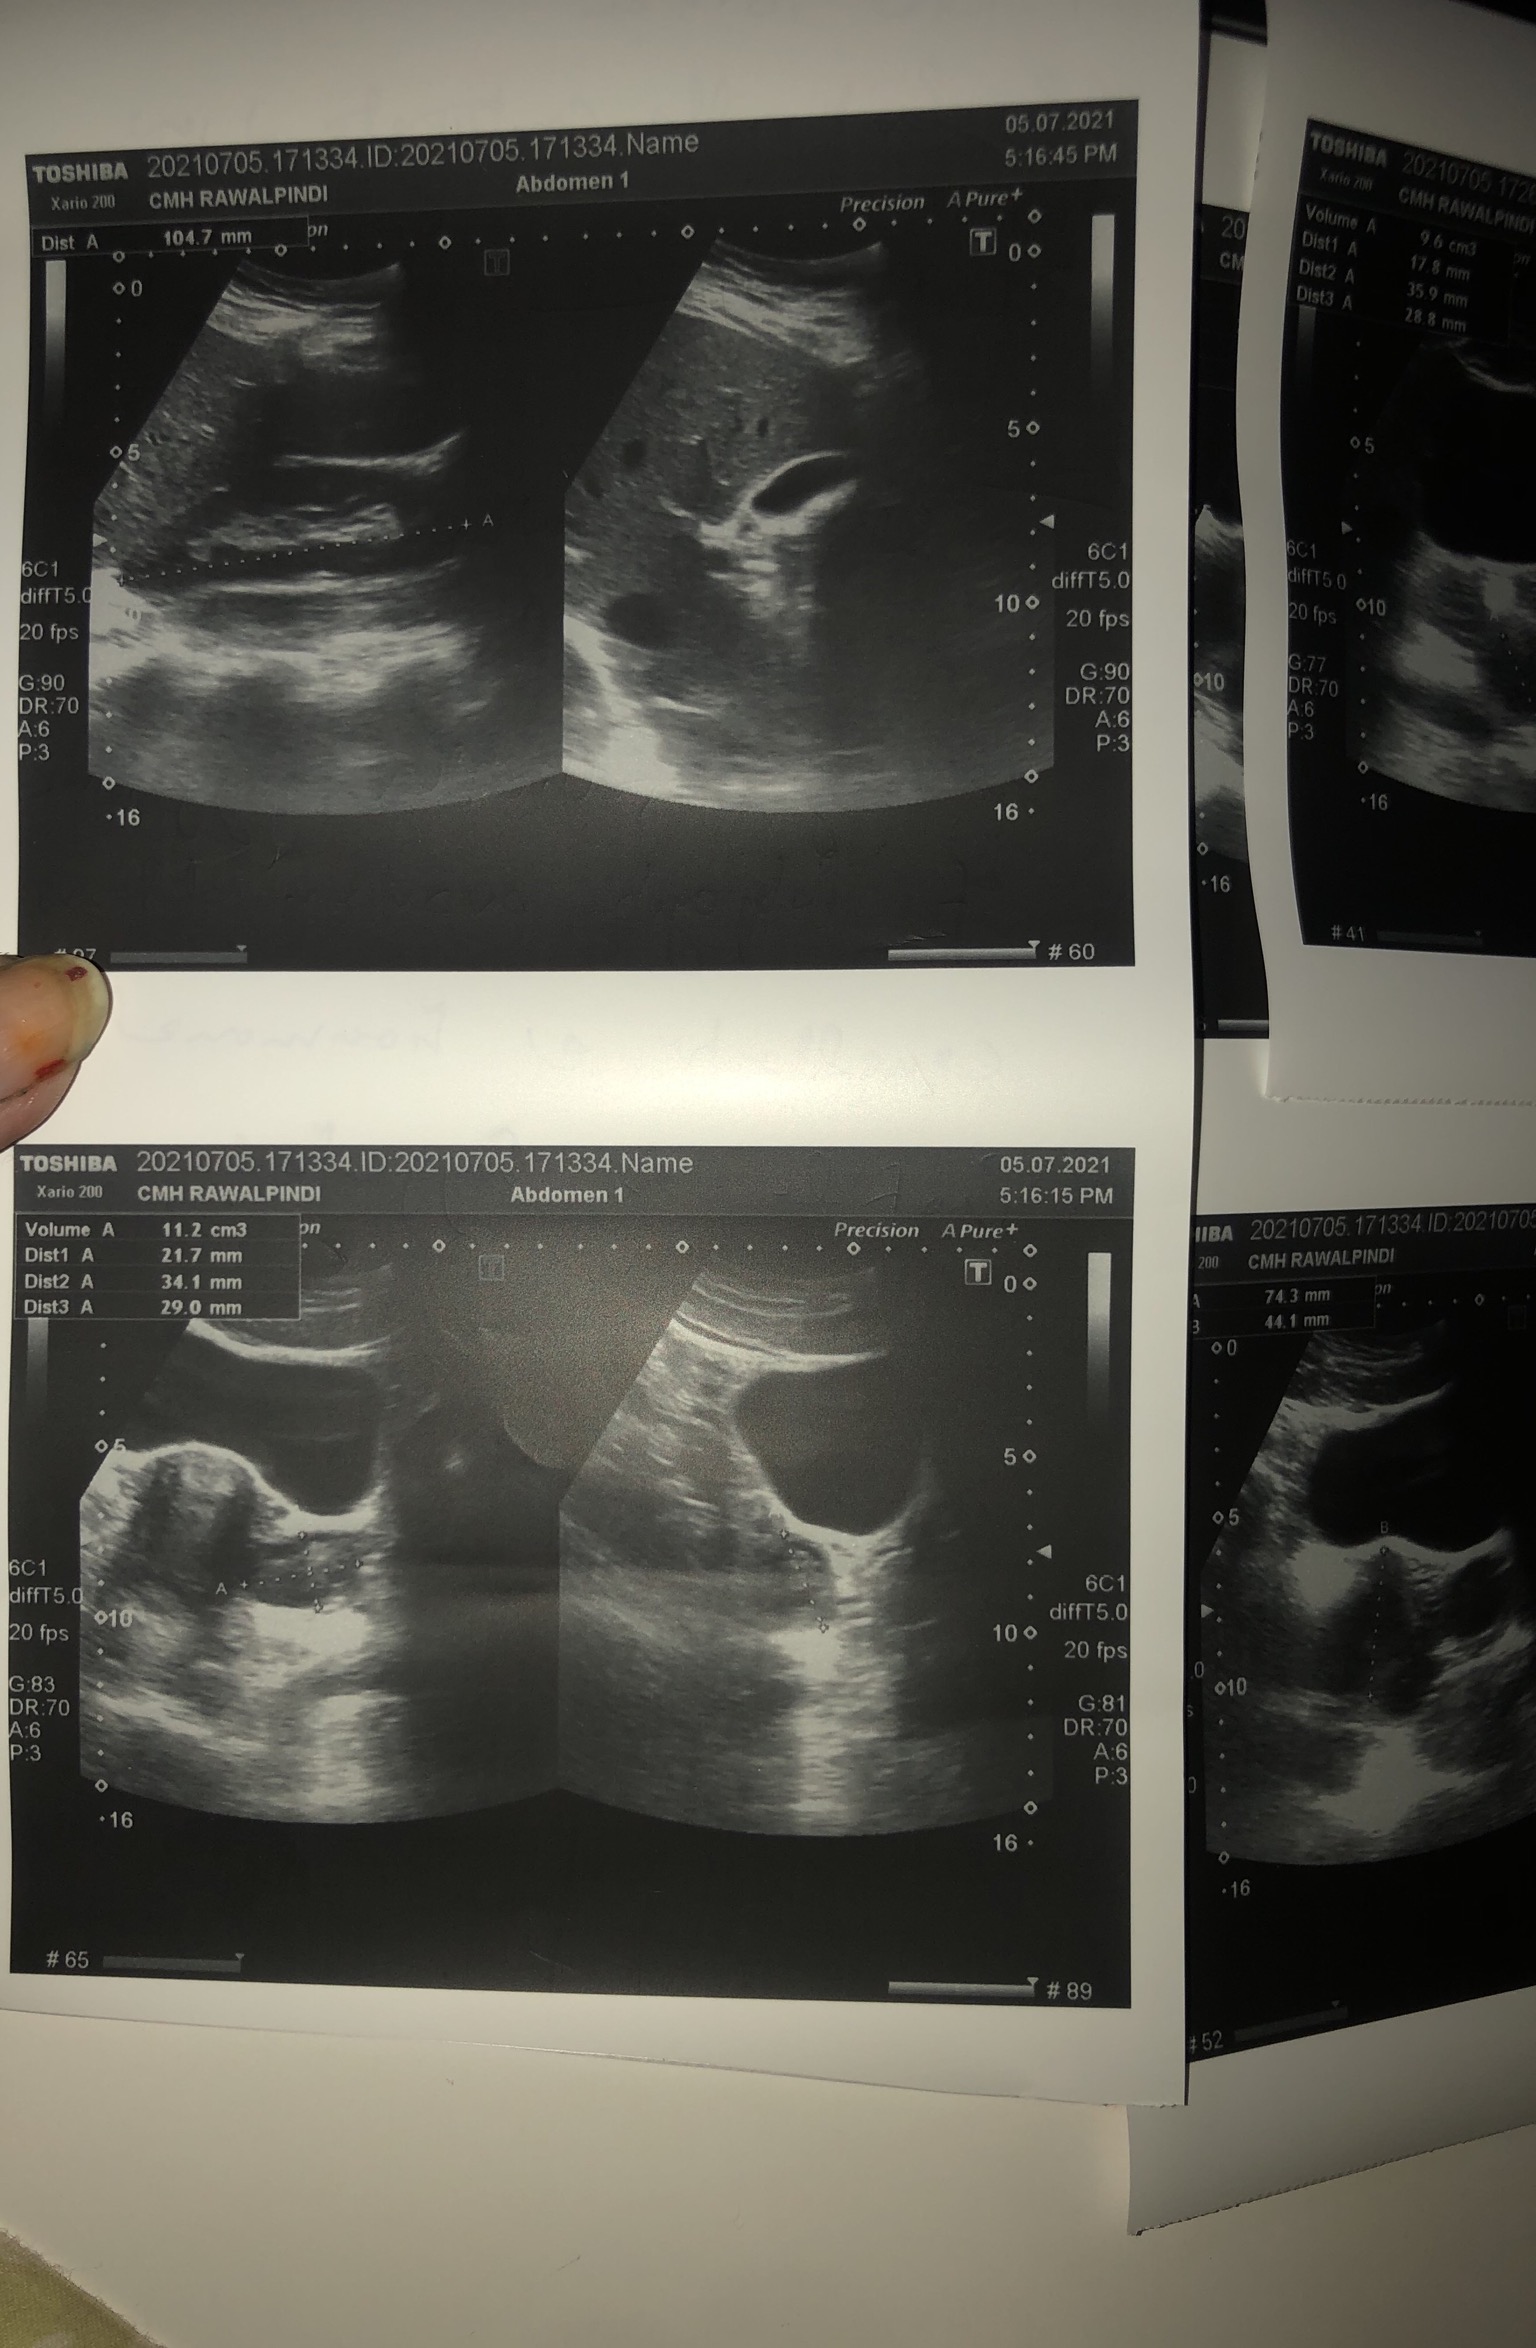

Asking for Self, Female, 28 years old, Rawalpindi

Plz help read my repirts and any treatment

Aoa your scan report and periods pattern suggestive of pcos. You need diet exercise and consultation. So you can understand and manage your problem. Thank you